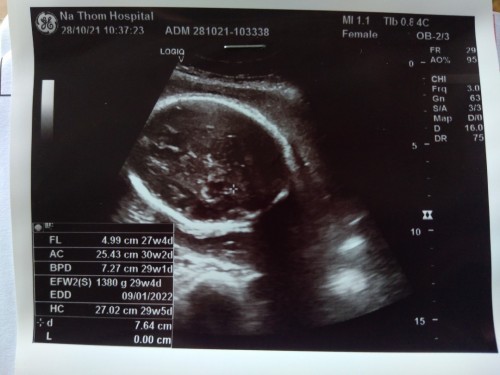

ตั้งครรภ์30วีคน้ำหนักตัวลูกอย่างต่ำควรยุที่เท่าไรคะ

แม่บ้านนี้มีภาวะเบาหวานขณะตั้งครรภ์ ต้องคุมน้ำตาล คุมอาหารทุกอย่าง ตั้งแต่เริ่มตั้งท้องมาจนถึง30วีคน้ำหนักเพิ่มขึ้น 7กิโล แม่ๆบ้านไหนเป็นเบาหวานขณะตั้งครรภ์ แล้วน้ำหนักตัวน้องประมาณเท่าไรกันบ้างคะ

เราเป็นเบาหวานเหมือนกันค่ะ ตรวจเจอช้าด้วย วีคที่ 32 แล้วที่เจอ หมอให้คุมอาหาร นน.ตัวไม่ค่อยขยับเลยค่ะ แต่นน.ลูกตอนนี้ 33 วีค+5 อยู่ที่ 2,000 กรัม หมอบอกว่ายังอยู่ในเกณฑ์ปกติค่ะ

คุมน้ำตาลตั้งแต่13Wตอนนี้30w น้ำหนักขึ้นมา5โล แต่น้องน้ำหนักตรวจตอน29w เกินเกณปาไป1700แล้วจ้า

เรา30วีคเหมือนกันแต่ไม่เป้นเบาหวาน ตอนนี้น้องหนัก 1330กรัมค่ะ